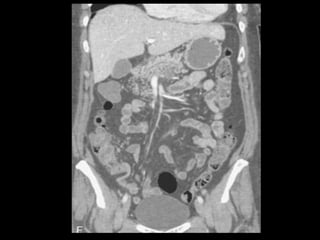

A TCMD pancreática bifásica consiste em uma fase

do parênquima pancreático(FP) e uma fase venosa

portal(FVP);

Fase portal: ↓ sensibilidade para T, mas ↑

sensibilidade para invasão vascular.

Os retardos de exame para a FP e a FVP podem ser

fixos ou individualizados;

Na primeira abordagem:

Retardo de exame de 40 e de 70 segundo para a FP e a

FVP respectivamente.

Preferência: retardo individualizado.

TCMD de 16 ou 64: 150 ml de contraste, razão de fluxo

de 8 ml/ s, 500 ml de água 20-30 min antes e 250 ml

imediatamente antes do exame;

Fase sem contraste: detectar calcificações e

determinar claramente a localização e extensão do

pâncreas.